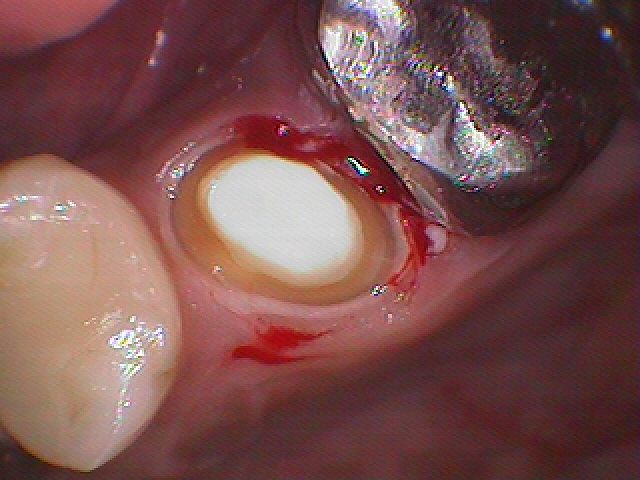

このようにクラウンが入っています

5番は根の治療から行いファイバーコアにて土台を立てています

5番のセラミックを入れて次は6番のクラウンを外していきます